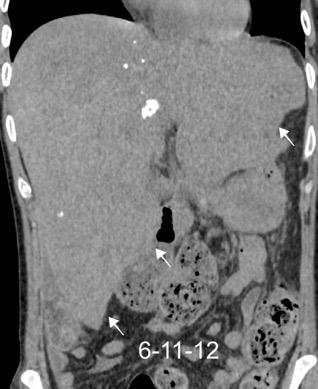

Paciente que ingresa con síntomas de colecistitis aguda. Antecedentes de trauma importante muchos años antes

Zhao L et al. Delayed traumatic diaphragmatic rupture: diagnosis and surgical treatment. © Journal of Thoracic Disease.

J Thorac Dis 2021

Asas

Líquido pericolecistítico

V. biliar con cálculos

Diafragma